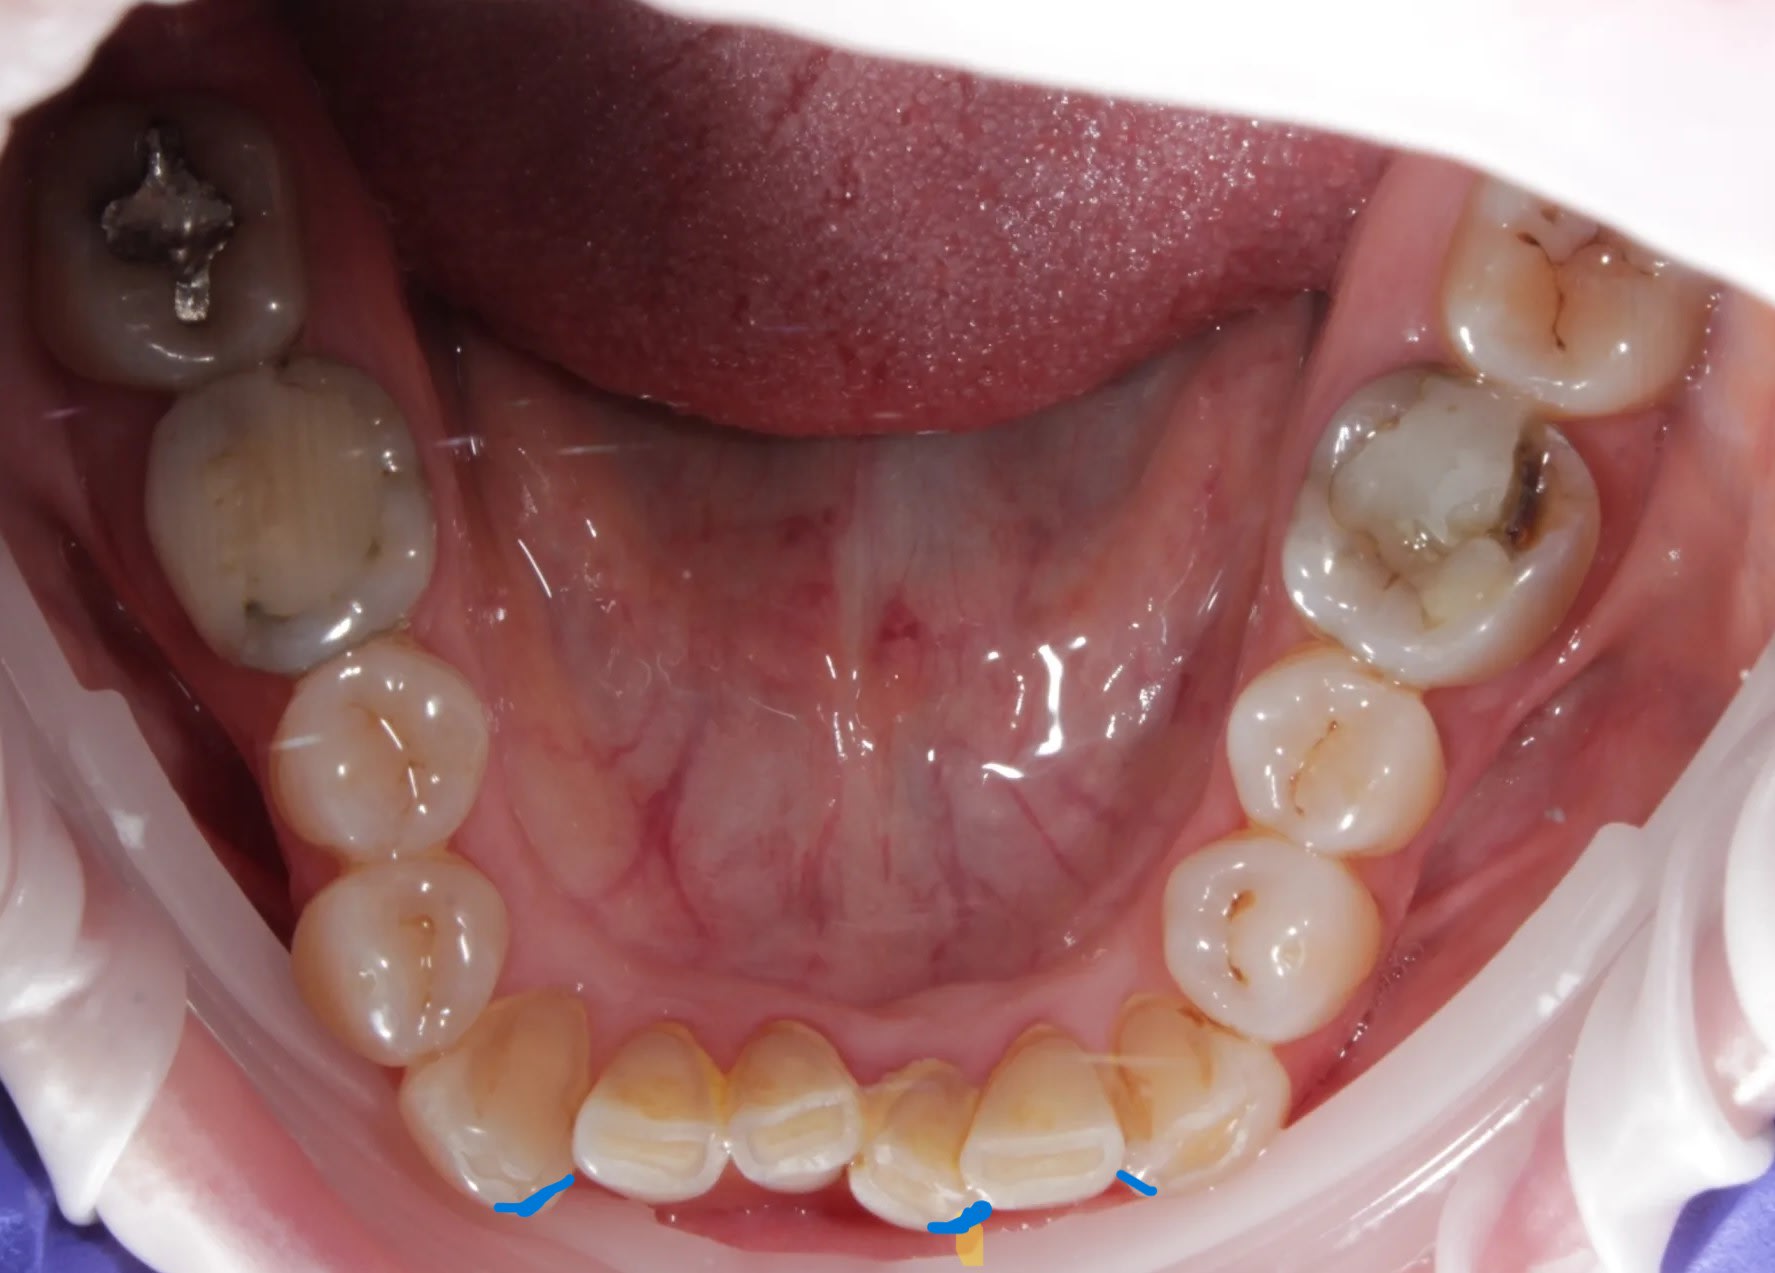

photos

par contre si tu lui limes les points bleus , terminé son hypertonicité .